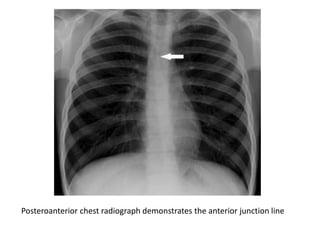

Anterior Junction Line

• The line is formed by the anterior apposition of the

lungs and consists of the four layers of pleura

separating the lungs behind the upper two-thirds of

the sternum.

• The line runs obliquely from upper right to lower left

and does not extend above the manubriosternal

junction.

• Contains variable amount of fat.

Posteroanterior chest radiograph demonstrates the anterior junction line